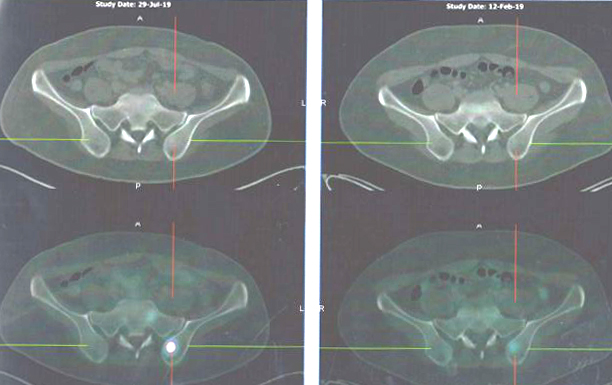

Mari kita lihat hasil pemindaian PET-nya.

Perbandingan hasil pemindaian: 29 Juli 2019 (baris atas) vs 12 Februari 2019 (baris bawah)

Perbandingan hasil pemindaian: 29 Juli 2019 (baris kiri) vs 12 Februari 2019 (baris kanan)

Ada yang salah dengan tulangnya? Pemindaian pada 29 Juli 2019 (kolom kiri) tampaknya lebih serius daripada pemindaian yang dilakukan pada 12 Februari 2019 (kanan).

Hasil PET scan pada 29 Juli 2019